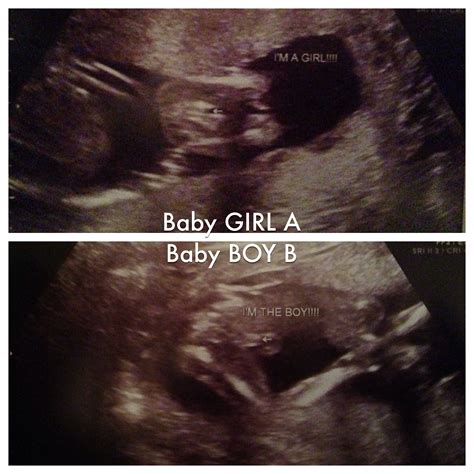

• Gender Determination: If you wish to know your baby's gender, this ultrasound is often the earliest time when it can be determined with reasonable accuracy. However, it's important to note that the accuracy can vary.

πŸ“ Note: The accuracy of gender determination can vary, and it's essential to discuss any concerns with your healthcare provider.